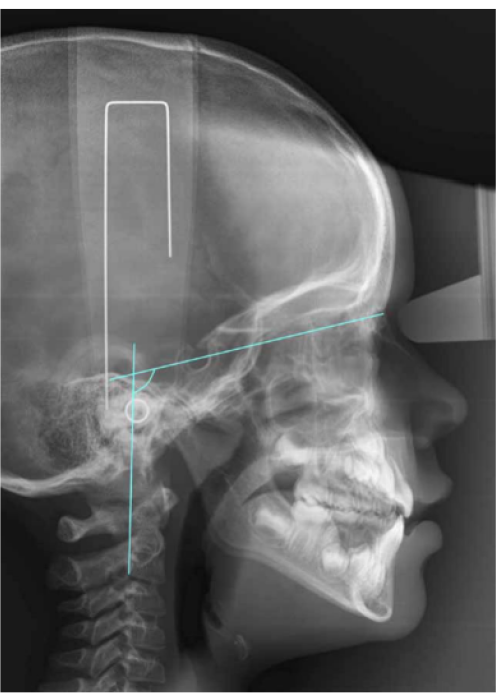

Características de la posición craneocervical con diferentes oclusiones en pacientes en desarrollo. Relación craneocervical y oclusión

Craniocervical position characteristics for different occlusions in developing patients: Craniocervical relationship and occlusion